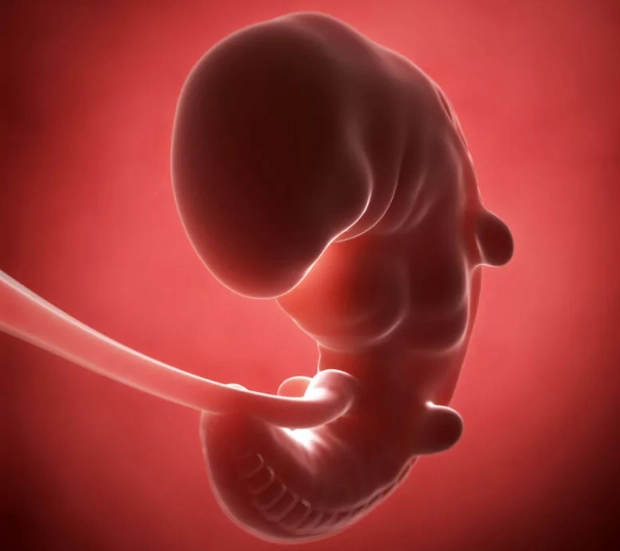

By the end of the fourth week (completing the first month), your little one—now called an embryo—is about the size of a poppy seed. Tiny, but busy.

Here's what's forming: The fertilized egg has rapidly divided into layers. One layer will become the brain, spinal cord, nerves, and skin. Another is busy forming the lungs, intestines, and bladder. The third is creating the heart, bones, muscles, and blood. The amniotic sac and yolk sac are already in place, providing protection and nourishment.

And the heart? This gets me every time. By around week 4, a primitive heart tube has formed and may even begin to beat, though it's too early to detect on an ultrasound. Think about that. In just a few weeks from a single cell, the blueprint for a human heart is already pulsing.